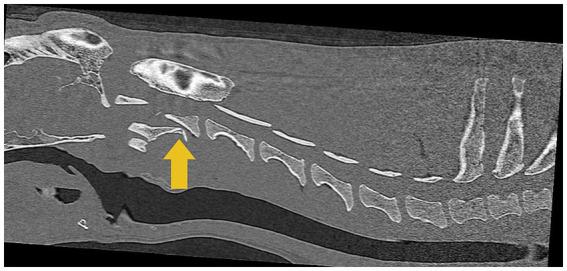

Veterinary cuttable plates (VCPs) were used to maintain reduction and provide reinforcement in screw and polymethylmethacrylate (PMMA) repairs of C2 vertebral fractures in two dogs. A 6-month-old male intact 3.8 kg Shih Tzu and a 4-year-old male intact 30.5 kg Golden Retriever presented after motor vehicle accidents. Computed tomography (CT) scans revealed fractures of the C2 vertebrae in both dogs. Fractures were reduced and stabilized with a combination of cortical screws, VCPs, and PMMA. The novel technique utilized veterinary cuttable plates positioned between screws cranial and caudal to the fracture for distraction and reduction of the fractures and can be incorporated into the acrylic. Post-operative imaging showed adequate fracture reduction and relief of spinal cord compression. Recheck examinations demonstrated a return to normal and near-normal neurologic function in both patients.

在两只犬的C2椎体骨折的螺钉和聚甲基丙烯酸甲酯(PMMA)修复中,使用兽医可切割钢板(VCP)来维持复位并提供加固。一只6个月大、体重3.8千克的未绝育雄性西施犬和一只4岁、体重30.5千克的未绝育雄性金毛寻回犬在机动车事故后就诊。计算机断层扫描(CT)显示两只犬均有C2椎体骨折。通过皮质螺钉、VCP和PMMA的联合使用,骨折得以复位并稳定。这项新技术利用置于骨折部位头侧和尾侧螺钉之间的兽医可切割钢板来牵引和复位骨折,并且可以与丙烯酸材料结合使用。术后影像学检查显示骨折复位良好,脊髓压迫得到缓解。复查显示两名患者的神经功能均恢复到正常或接近正常。